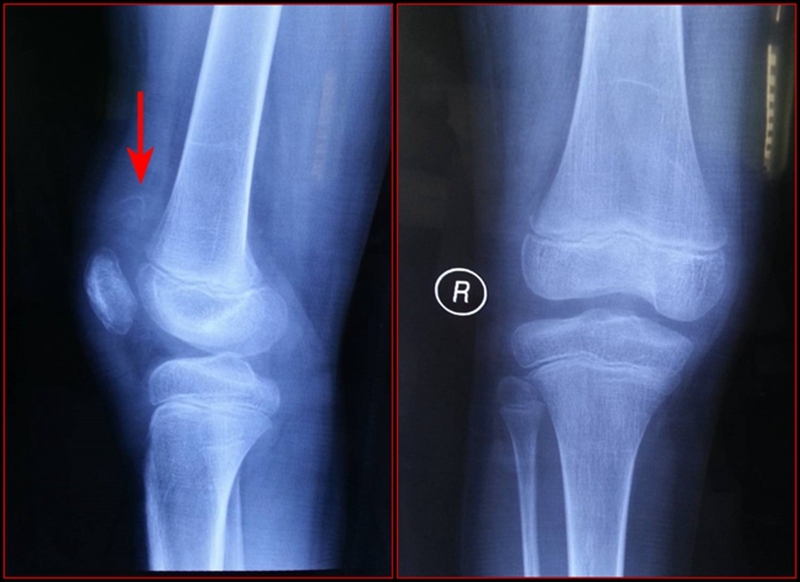

图3 受伤后3周MRI

考虑此患儿伤后已3周,组织全科讨论,确定诊断为:髌骨上极陈旧性套状撕脱骨折。充分与家属沟通远期预后。

1.髌骨上、下极的斑片、点状薄层骨组织影像或半环、新月形骨块阴影,同时还应注意髌骨有否高位、低位及髌韧带、股四头肌腱软组织影是否松弛。

2.X线片无骨性组织显影时,应予以MRI扫描。